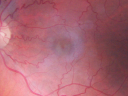

OD: Vertical C/D ratio is 0.1. There is no posterior vitreous separation. There is a grey tint to the retina. There are telangiectatic vessels temporal to the fovea and retinal crystals just on the temporal edge of the fovea.